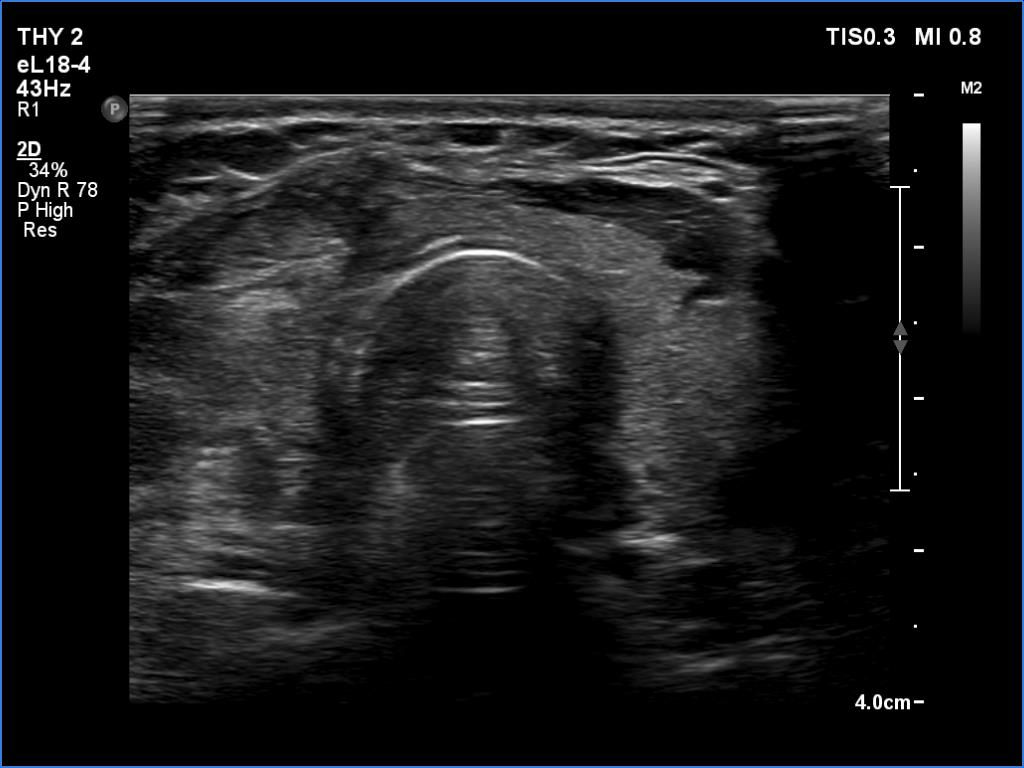

Four weeks after the surgery (ultrasonographic picture 4)

The thyroid, transverse scan. The right lobe was removed while the isthmus and the left lobe was left inside. Note the difference between the regenerative and the healthy thyroid tissue.